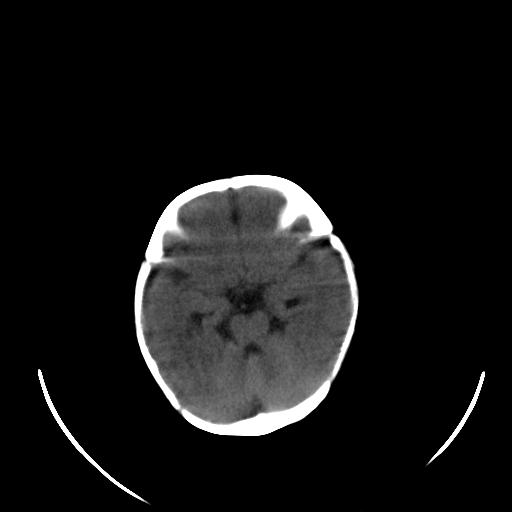

患儿 女性 1个月  今天发现阵发性抽搐  双眼上翻、凝视,嘴唇及面色青紫

考虑双侧脉络膜裂囊肿。

双侧颞枕叶片状低密度影,考虑新生儿却血缺氧性脑病可能

左侧额叶见班片样低密度灶,症状像癫痫,可能与之有关。

新生儿却血缺氧性脑病不排除!

左侧额叶见班片样低密度灶,建议mr

考虑hie。

考虑新生儿hie。